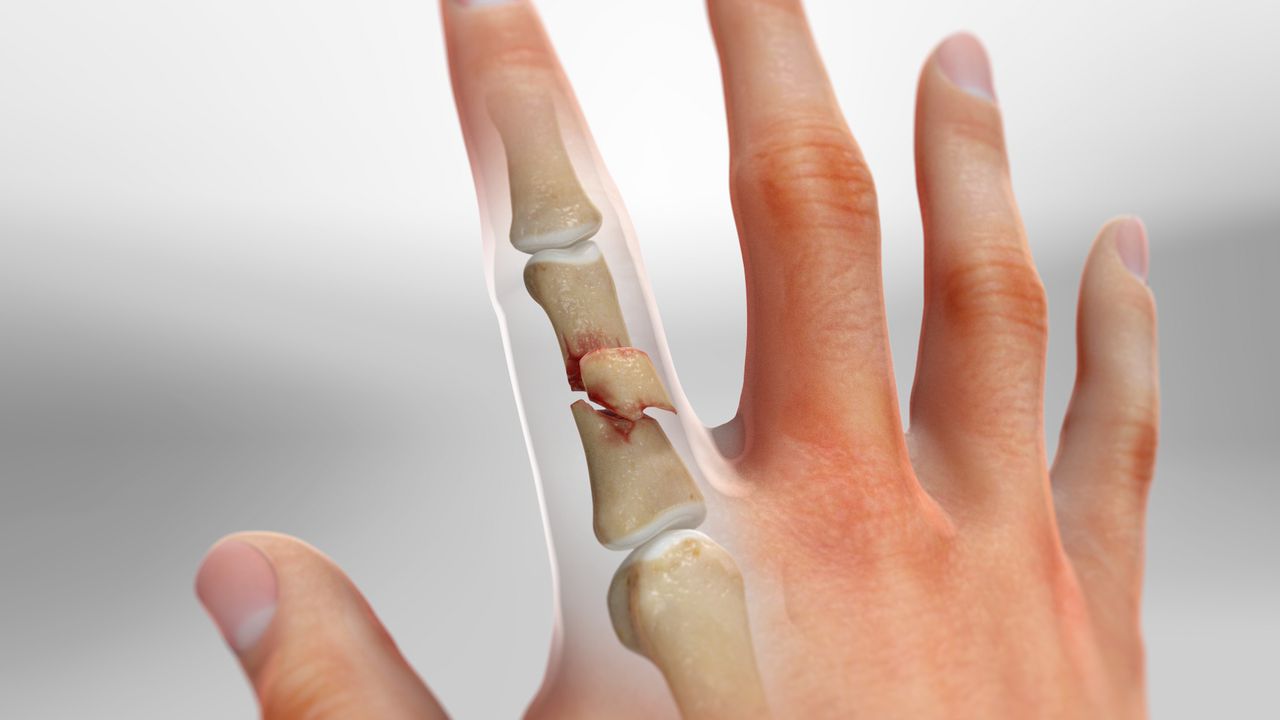

손가락 뼈에 금이 간 경우, 그 정도에 따라 치료 방법이 달라질 수 있습니다.

- 단순 골절: 뼈가 깨지지 않고 비교적 완만하게 금이 간 경우에는 깁스로 고정해주기만 해도 충분할 수 있습니다.

- 복합 골절: 뼈가 여러 조각으로 깨져 있는 경우에는 핀이나 금속판을 사용하여 뼈를 고정해야 할 수 있습니다.

- 비스듬한 골절: 뼈가 비스듬하게 부러진 경우에도 핀을 사용하여 고정하는 것이 일반적입니다.